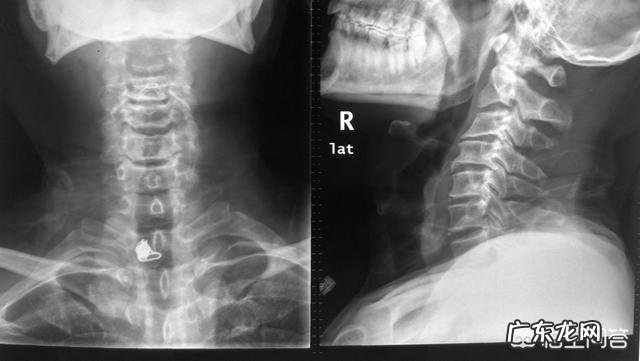

“电脑族”该怎样预防颈椎病颈椎由7个椎体和6个椎间盘组成,椎间盘就是骨头之间的缓冲垫子 。

颈椎的活动范围是全脊柱活动范围最大的部分 。头的屈伸活动主要是寰枢关节的转动(第1/2颈椎之间的活动),颈部的屈曲和后伸主要是下位颈椎在起作用 。颈椎是一个整体,任何一个节段活动发生障碍,相邻的颈椎各关节及韧带所承受的应力均明显增加,从而导致关节、椎间盘、韧带的退行性变 。出现各种症状 。